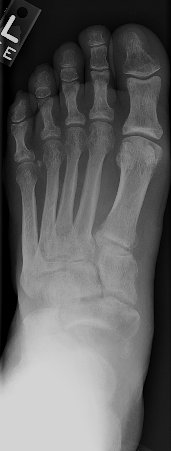

Return to Basketball Foot (Subtalar Dislocation)